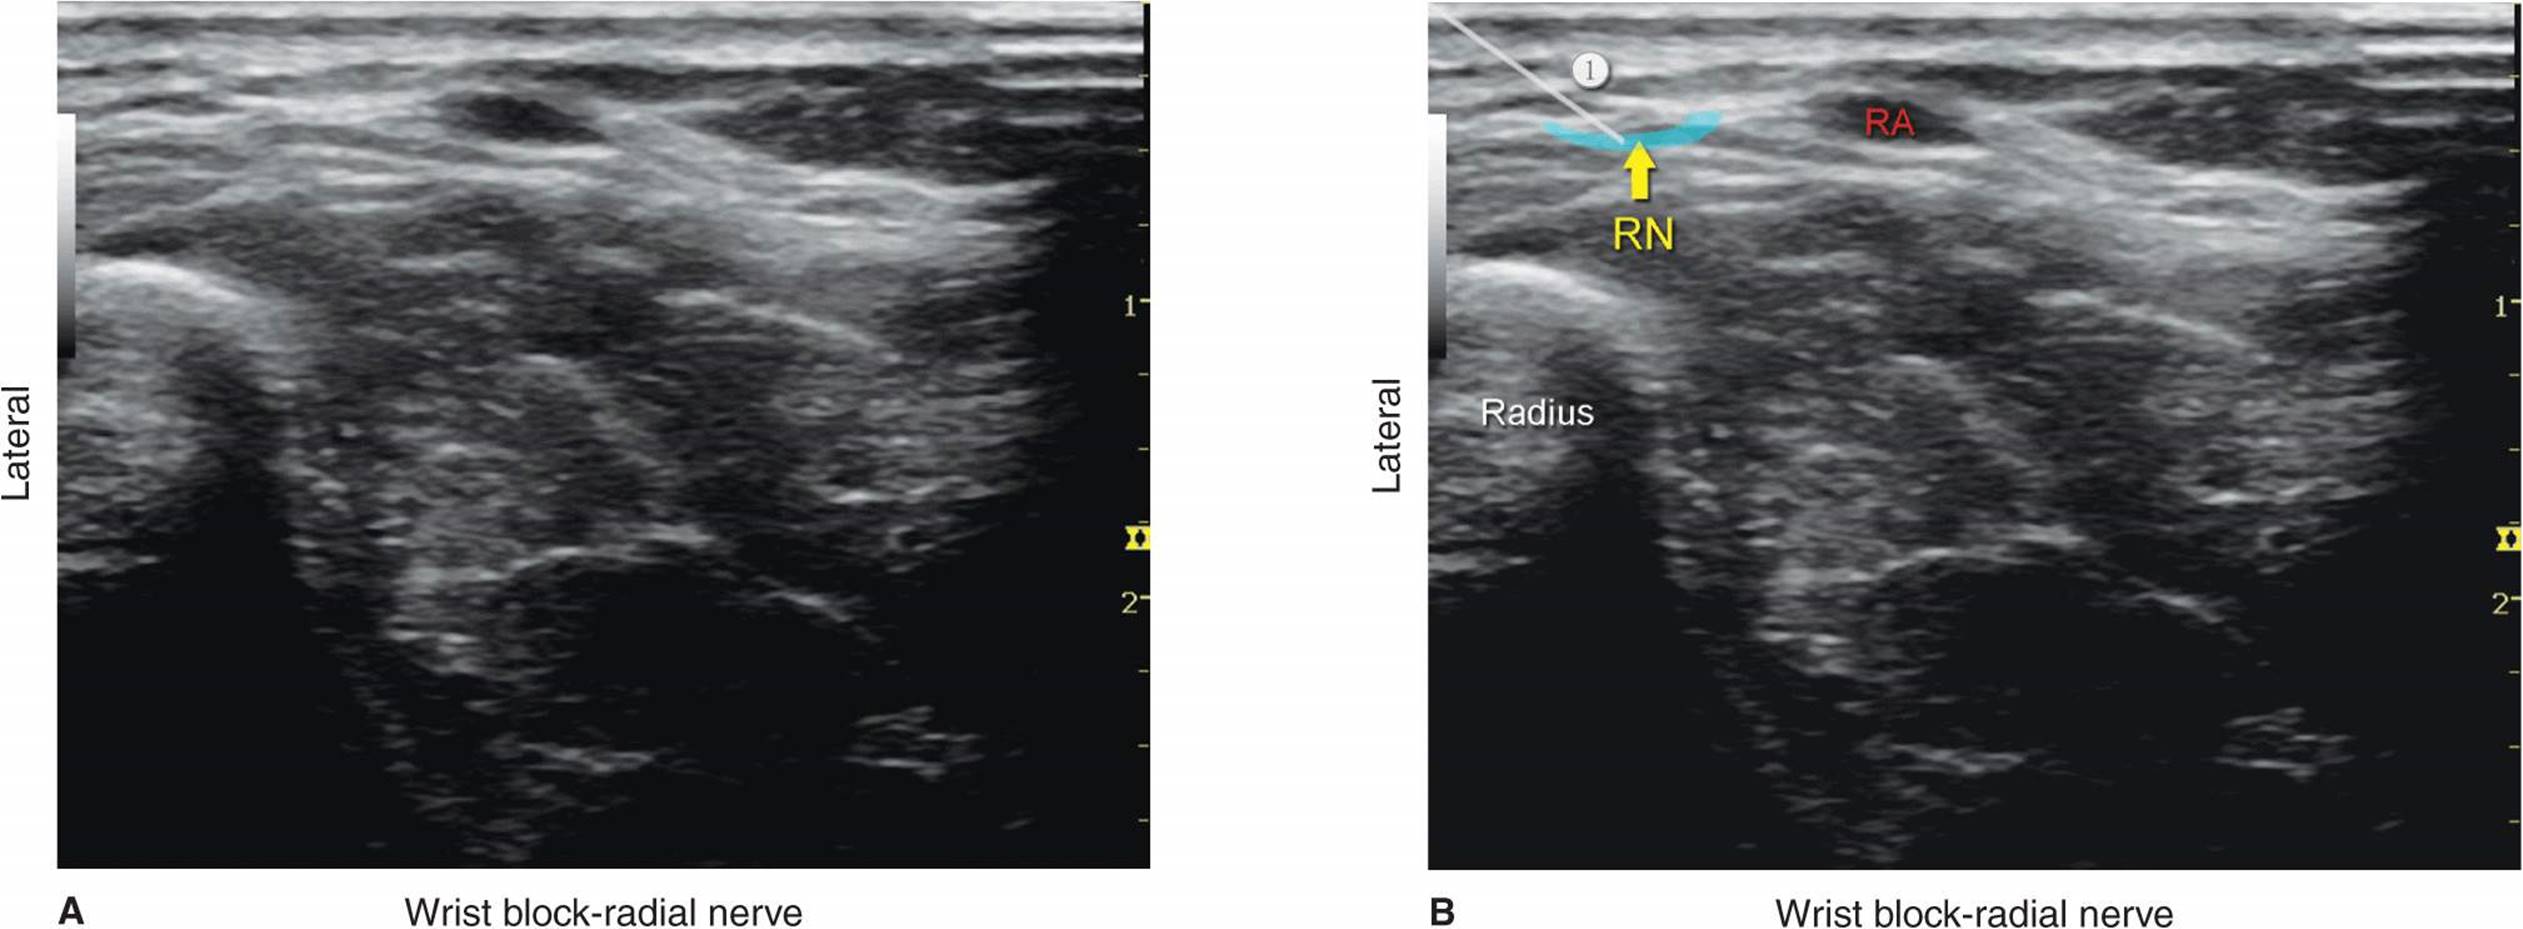

The superficial branch of the radial nerve divides into terminal branches at the level of the wrist; for this reason, ultrasonography is not very useful for guidance for placement of the block at the level of the wrist. A subcutaneous field block around the area of the styloid process of the radius remains an easy method to perform an effective radial nerve block at the level of the wrist (refer to the wrist block in Chapter 16). However, ultrasonography can be used at the elbow level or in the midforearm. At the level of the elbow (slightly below the elbow), the nerve is easily identified as a hyperechoic oval or triangular structure in the layer between the brachialis (deep) and brachioradialis (superficial) muscles lateral to the radial artery (Figures 34-6A and B and 34-7A and B).

FIGURE 34-6. (A) Block of the radial nerve (RN) at the wrist. Transducer and needle position. (B) Cross-sectional anatomy of the RN at the wrist level. Superficial branches of the radial nerve are highly variable at this level in number, size, and depth. For that reason, block of the RN at the wrist is not an exact technique but rather infiltration of the local anesthetic in the subcutaneous tissue and underneath the superficial fascia.

FIGURE 34-7. (A) Sonoanatomy of the radial nerve (RN) at the level of the wrist. (B) One branch of the RN at the wrist is shown lateral to the radial artery (RA), and the approximate needle path to reach a branch of the radial nerve is shown with an approximate spread of local anesthetic (area shaded in blue) to anesthetize it.